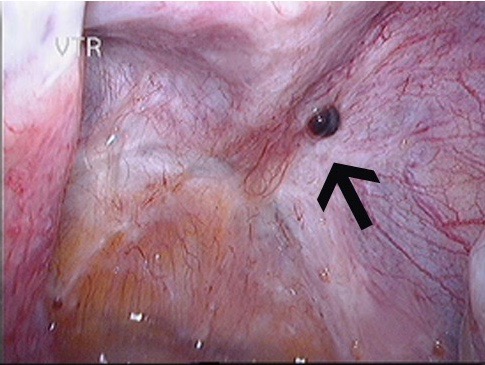

Both images below show deep infiltrating endometriosis with significant adhesions. Organs are stuck together.

In about 20% of women with endometriosis, the endometriosis will not just superficially implant in the pelvis, but it will infiltrate into pelvic structures, mainly into bowel, bladder, the vagina and ligaments behind the uterus (uterosacral ligaments). This form of the disease is called deep infiltrating endometriosis (DIE). Deep infiltrating endometriosis causes usually more destruction of the normal anatomy and is generally significantly more difficult to remove. Because lesions of endometriosis infiltrate into ligaments, vagina, bowel and bladder, adhesions can occur between organs such as the bowel and the uterus or the uterus and the ovaries.